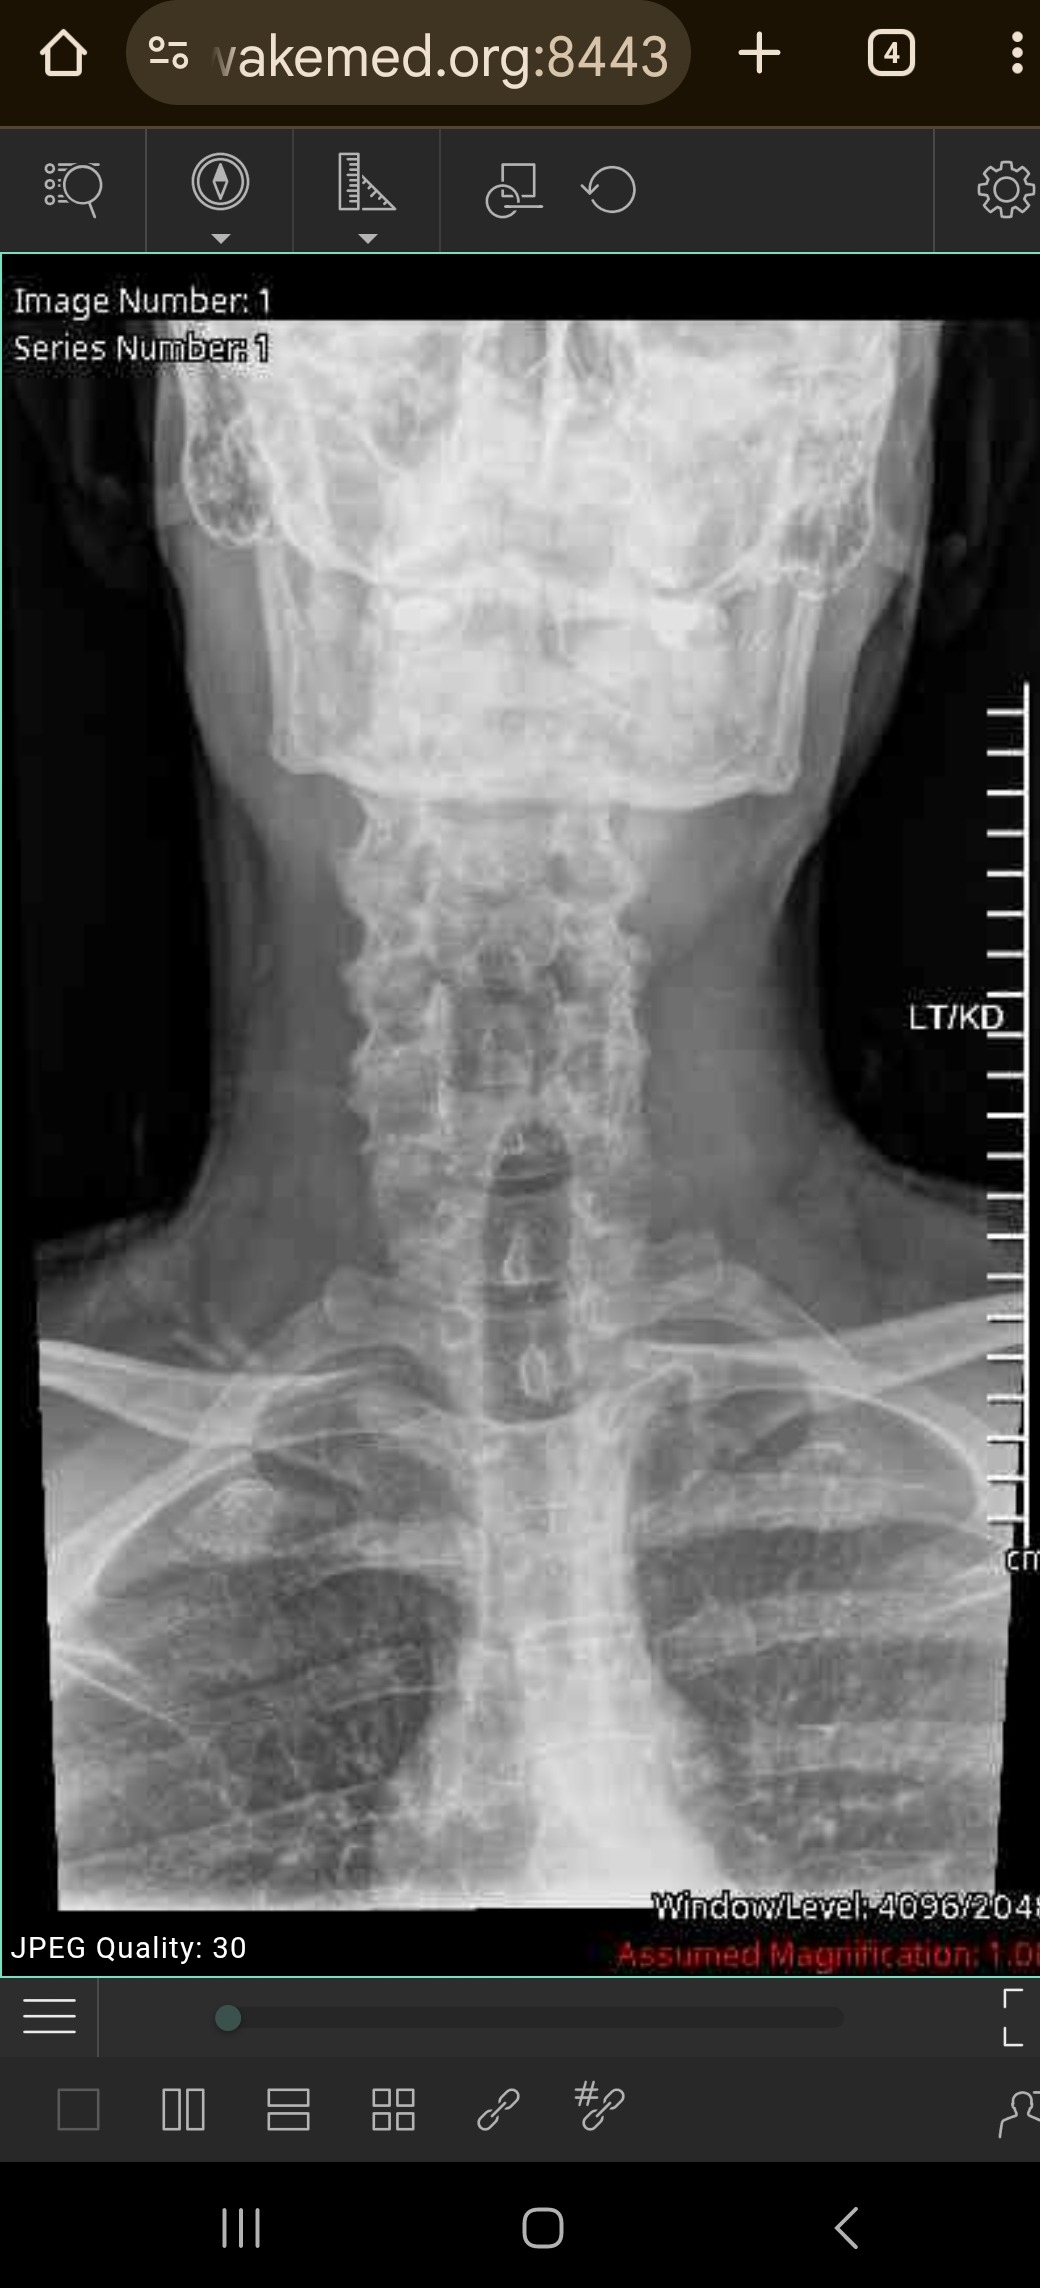

Almost 2 months ago, I herniated my C7 disc in my neck. I have already been through physical therapy to no avail, and I am in need of surgery. This has been the most excruciating process I have ever been through. Sleep hasn't come because of the pain.